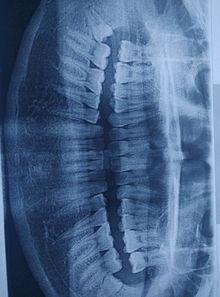

1. 智齿阻生:当智齿无法正常长出时,就会形成阻生智齿。这时,智齿会顶住周围的牙齿,导致牙龈红肿、疼痛,甚至引发感染。

1. 智齿阻生:这张图片展示了一颗阻生智齿,可以看到它顶住了旁边的牙齿,导致牙龈红肿。